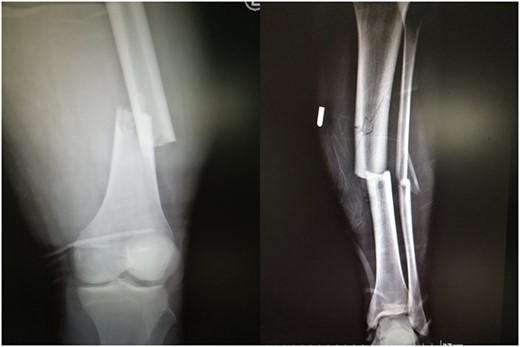

As soon as the patient woke up from the general anesthesia, he reported severe pain of the right uninjured calf. After 3 h, the pain became worse and unresponsive to strong analgesic medications. On examination, extreme swelling in the right calf was noticed. The pain was exacerbated with passive movements of the right toes and ankle. A progressive weakness of the anterior tibialis and the extensor hallucis longus muscle was noticed as well. The diagnosis of the right uninjured tibia compartment syndrome owing to the lithotomy position was confirmed and the patient underwent the appropriate fasciotomies 6 h after the initial operation. The shoelace surgical technique (Fig. 3) was performed for gradual closure of the compartments. Six months post-operation, the patient has gained 5/5 motor strength of the anterior tibialis and 3/5 of the extensor hallucis longus muscle, with no sensory deficits. A left femoral and tibia nail dynamization has been performed because of the fracture delayed union.

Progressive closure of the right uninjured tibia open compartments using the shoelace technique.